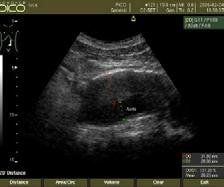

Stabilirea indicaţiei tratamentului endovascular cu DEBDOX necesită o pre-evaluare CT (“triple-phase”) sau IRM cu contrast, coroborată cu manifestările clinice și a datelor de laborator (AFPdeterminare cantitativă folosită ulterior în dinamica pentru evaluare, follow-up). Fiecare flacon de microsfere va fi încărcat cu 50-75 mg de Doxorubicin (doza de încărcare 25-37,5 mg Doxorubicin/ ml de microsfere)